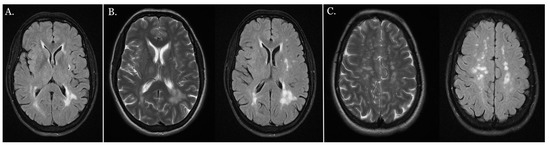

An MRI of the central nervous system showed multiple focal vasogenic lesions in the white matter of both hemispheres, which were partly merged in the occipital horn region (Figure 7B). A single microinfarct lesion was found in the left external capsule (Figure 7A).

Figure 7.

MRI of the central nervous system. (A) Single focal subcortical microinfarct in the left external capsule shown in MRI-FLAIR image. (B) Subcortical and periventricular areas of the white matter of the brain shown using MRI, along with multiple focal vasogenic lesions in the white matter of both hemispheres, partly merged in the occipital horn region (LS: MRI-T2 image, RS: MRI-FLAIR image). (C) The formation of pathological changes mainly in the white matter of the brain shown in MRI (left side (LS): MRI-T2 image, right side (RS) MRI-FLAIR image).